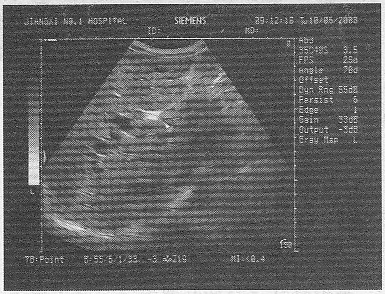

2.男,47歲,上腹部疼痛不適、腹脹,皮膚鞏膜黃疸,進行性加重,皮膚瘙癢。聲像圖如圖所示,最可能的診斷為

正確答案:C 解題思路:腹部疼痛不適、腹脹,皮膚鞏膜黃染,進行性加重,皮膚瘙癢,聲像圖顯示肝門部結構雜亂,可見一低回聲光團,肝內膽管擴張。